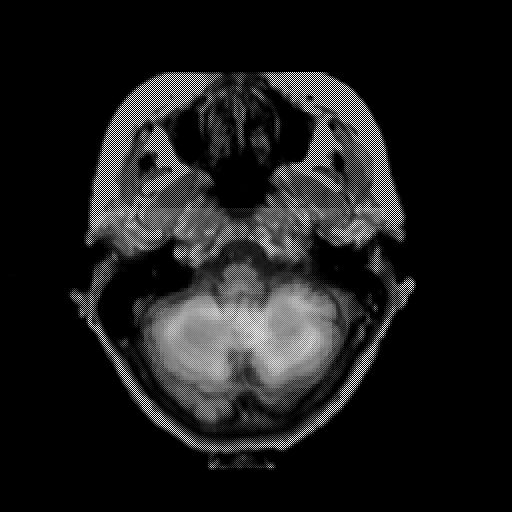

overlay: Slice 11

Slice 11

MRCBFCBF with

T1PDT2T1PDT2